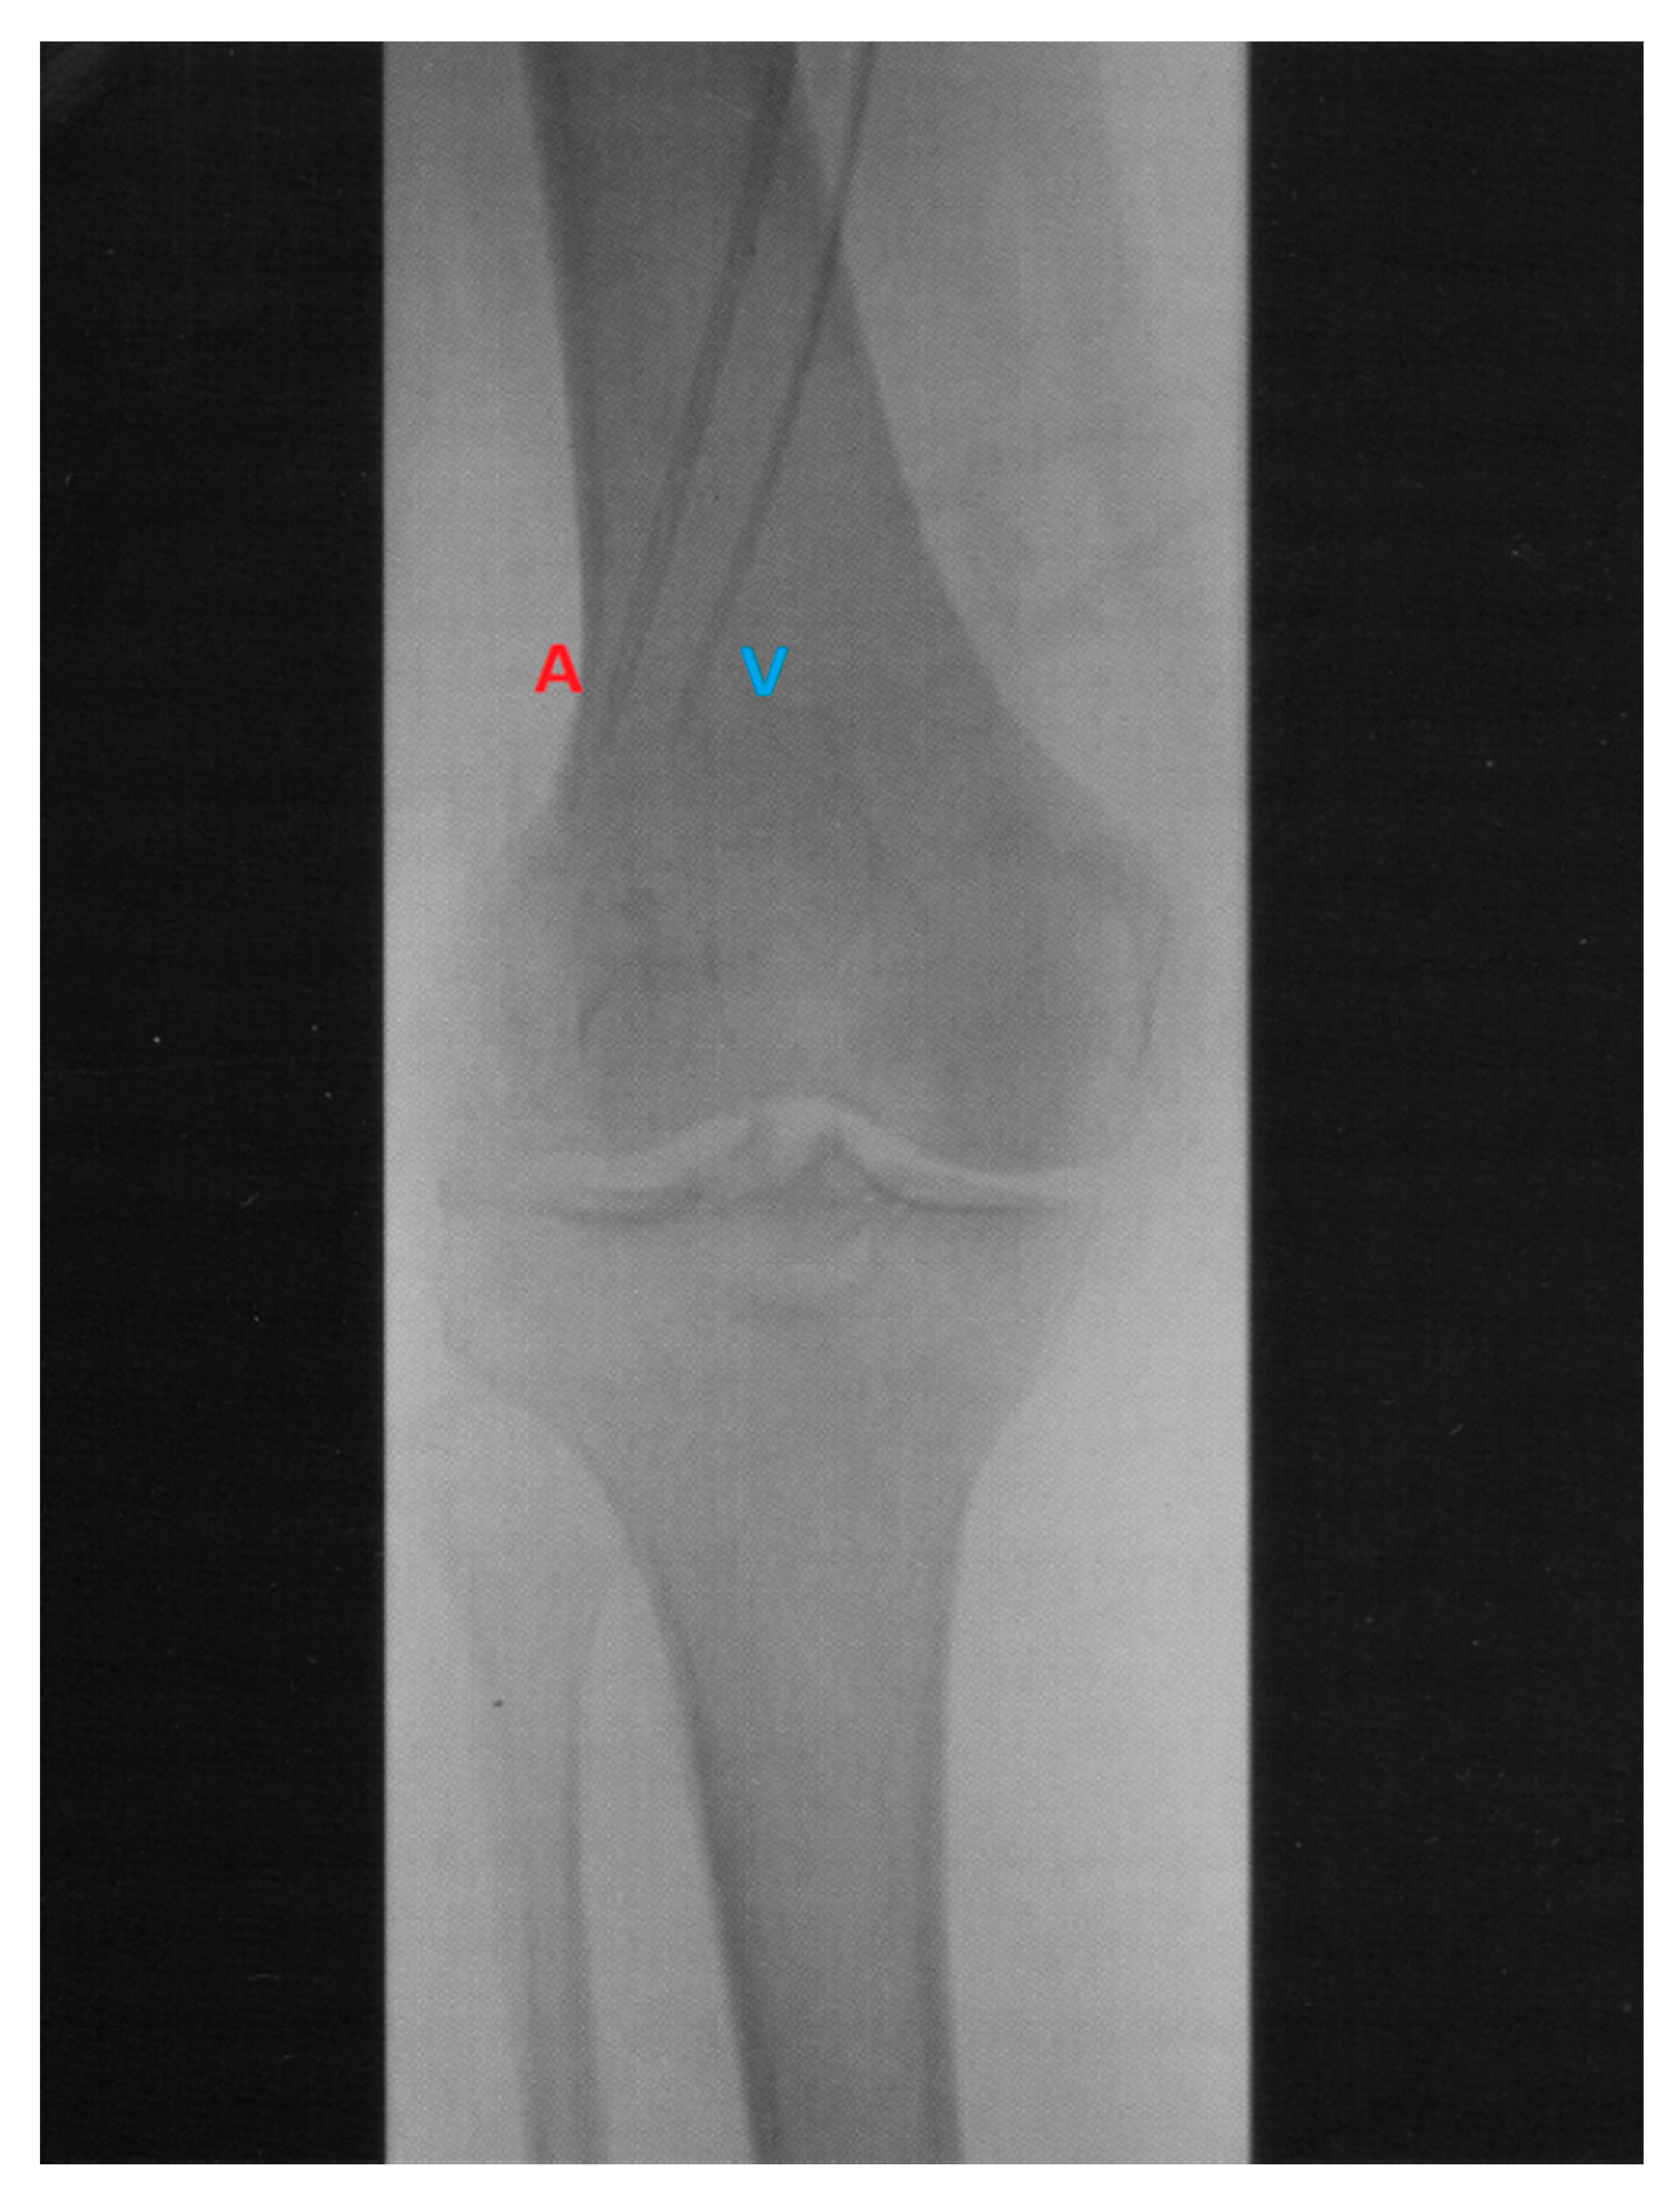

| Hyperthermic Isolated Limb Perfusion | Isolated Limb Infusion |

|---|---|

| Technically complex | Technically simple |

| Open surgical exposure of vessels for catheter insertion | Percutaneous vascular catheter insertion in radiology department |

| 4 to 6 h duration | Approximately 1 h |

| Perfusionist and ancillary staff required | No perfusionist required and fewer total staff |

| Complex and expensive equipment needed | Equipment requirements modest |

| Magnitude of procedure excludes patients | Well tolerated by medically compromised, frail and elderly patients |

| Not possible in occlusive vascular disease | Can be performed selectively in occlusive vascular disease |

| Technically challenging to perform a repeat procedure | Not difficult to perform a repeat procedure |

| Systemic metastases normally a contraindication | Systemic metastases not a contraindication |

| Higher perfusion pressures predispose to systemic leakage | Low pressure system, effective vascular isolation with tourniquet |

| Limb tissues oxygenated, with normal blood gases maintained | Progressive hypoxia and acidosis |

| Hyperthermia (>41 °C can be achieved) | Usually not possible to raise limb temperature above 40 °C |

| General anesthesia (GA) required | Possible with regional anaesthesia, GA preferred. |